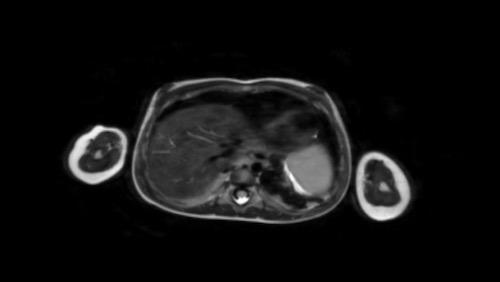

Same patient.

Đây là hình ảnh T1W axial có tiêm gadolinium với kỹ thuật xóa mỡ.

Hình ảnh cho thấy sự bao bọc của các mạch máu.

Lưu ý sự lan rộng của khối u ra phía sau động mạch chủ, đẩy động mạch chủ ra xa cột sống (mũi tên).